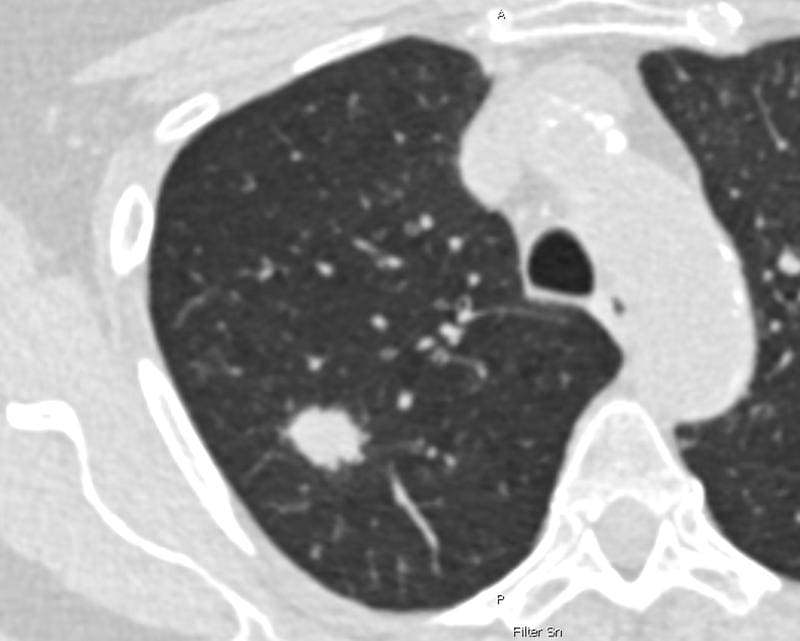

Every year, about 57,000 people in Germany are diagnosed with lung cancer, often with a fatal outcome, as the disease is usually discovered too late. The planned program is intended to check suspicious lung changes in high-risk people using computed tomography (CT). So far, participants between the ages of 50 and 75 who have smoked heavily for at least 25 years and either still smoke or quit less than ten years ago are planned, whereby tobacco consumption must mathematically result in at least 15 pack years.

The results were compared with the planned criteria, which only take into account age and smoking history (NELSON score). All people at high risk after one of the scores had two low-dose CT scans performed at annual intervals. Suspected cases were examined in interdisciplinary conferences and dealt with if confirmed.

In about 4,200 active or former smokers screened after PLCOm2012, 108 lung cancer cases were found, 19.4 percent more than in the NELSON group with around 3,900 people and 85 cases. With the extended score, about six percent more people would have to be screened, but screening would be more efficient, as fewer CT examinations per diagnosis would be necessary, as Prof. Martin Reck, chief physician of the oncology focus at the LungenClinic Grosshansdorf, notes.